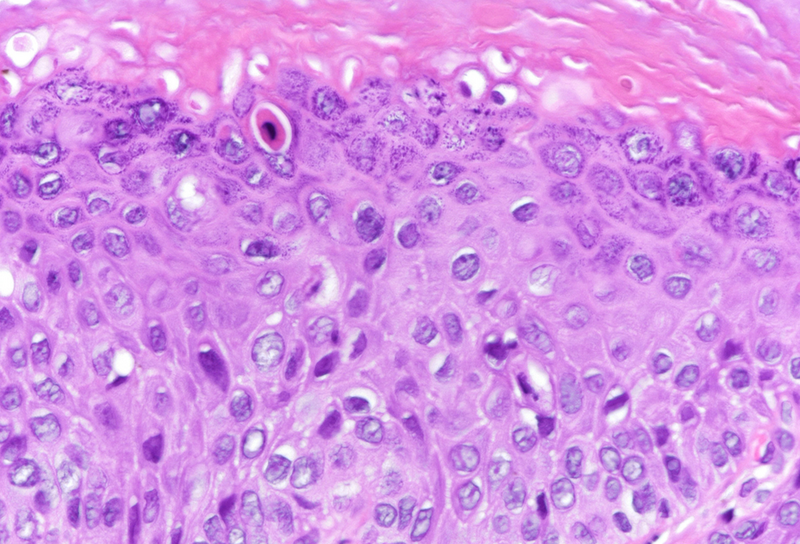

Microscopic examination revealed squamous dysplasia, affecting the full thickness of the epithelium (Panel A), with eventual koilocytes and increased apoptosis (Panel B). Mitotic figures were found throughout the epithelium, with marked increase in Ki-67 staining (Panel C). P16 immunohistochemistry reaction showed diffuse, block positivity which reached the excision margin (Panel D).

Histologically, cytological and architectural atypia is visible is at least half of the thickness of the epithelium. Koilocytes may be present, as well. Mitotic figures may often be found in the upper half of the epithelium. Diffuse, block positivity of p16 may reflect HPV genome internalization, however, the definitive diagnostic tool of identification is polymerase chain reaction (PCR). Regarding differential diagnosis, several reactive epithelial changes, and metaplasias may mimic HSIL, especially on small biopsy samples. In such cases, p16 may play even more crucial role. Naturally, invasion has to be ruled out in each case.